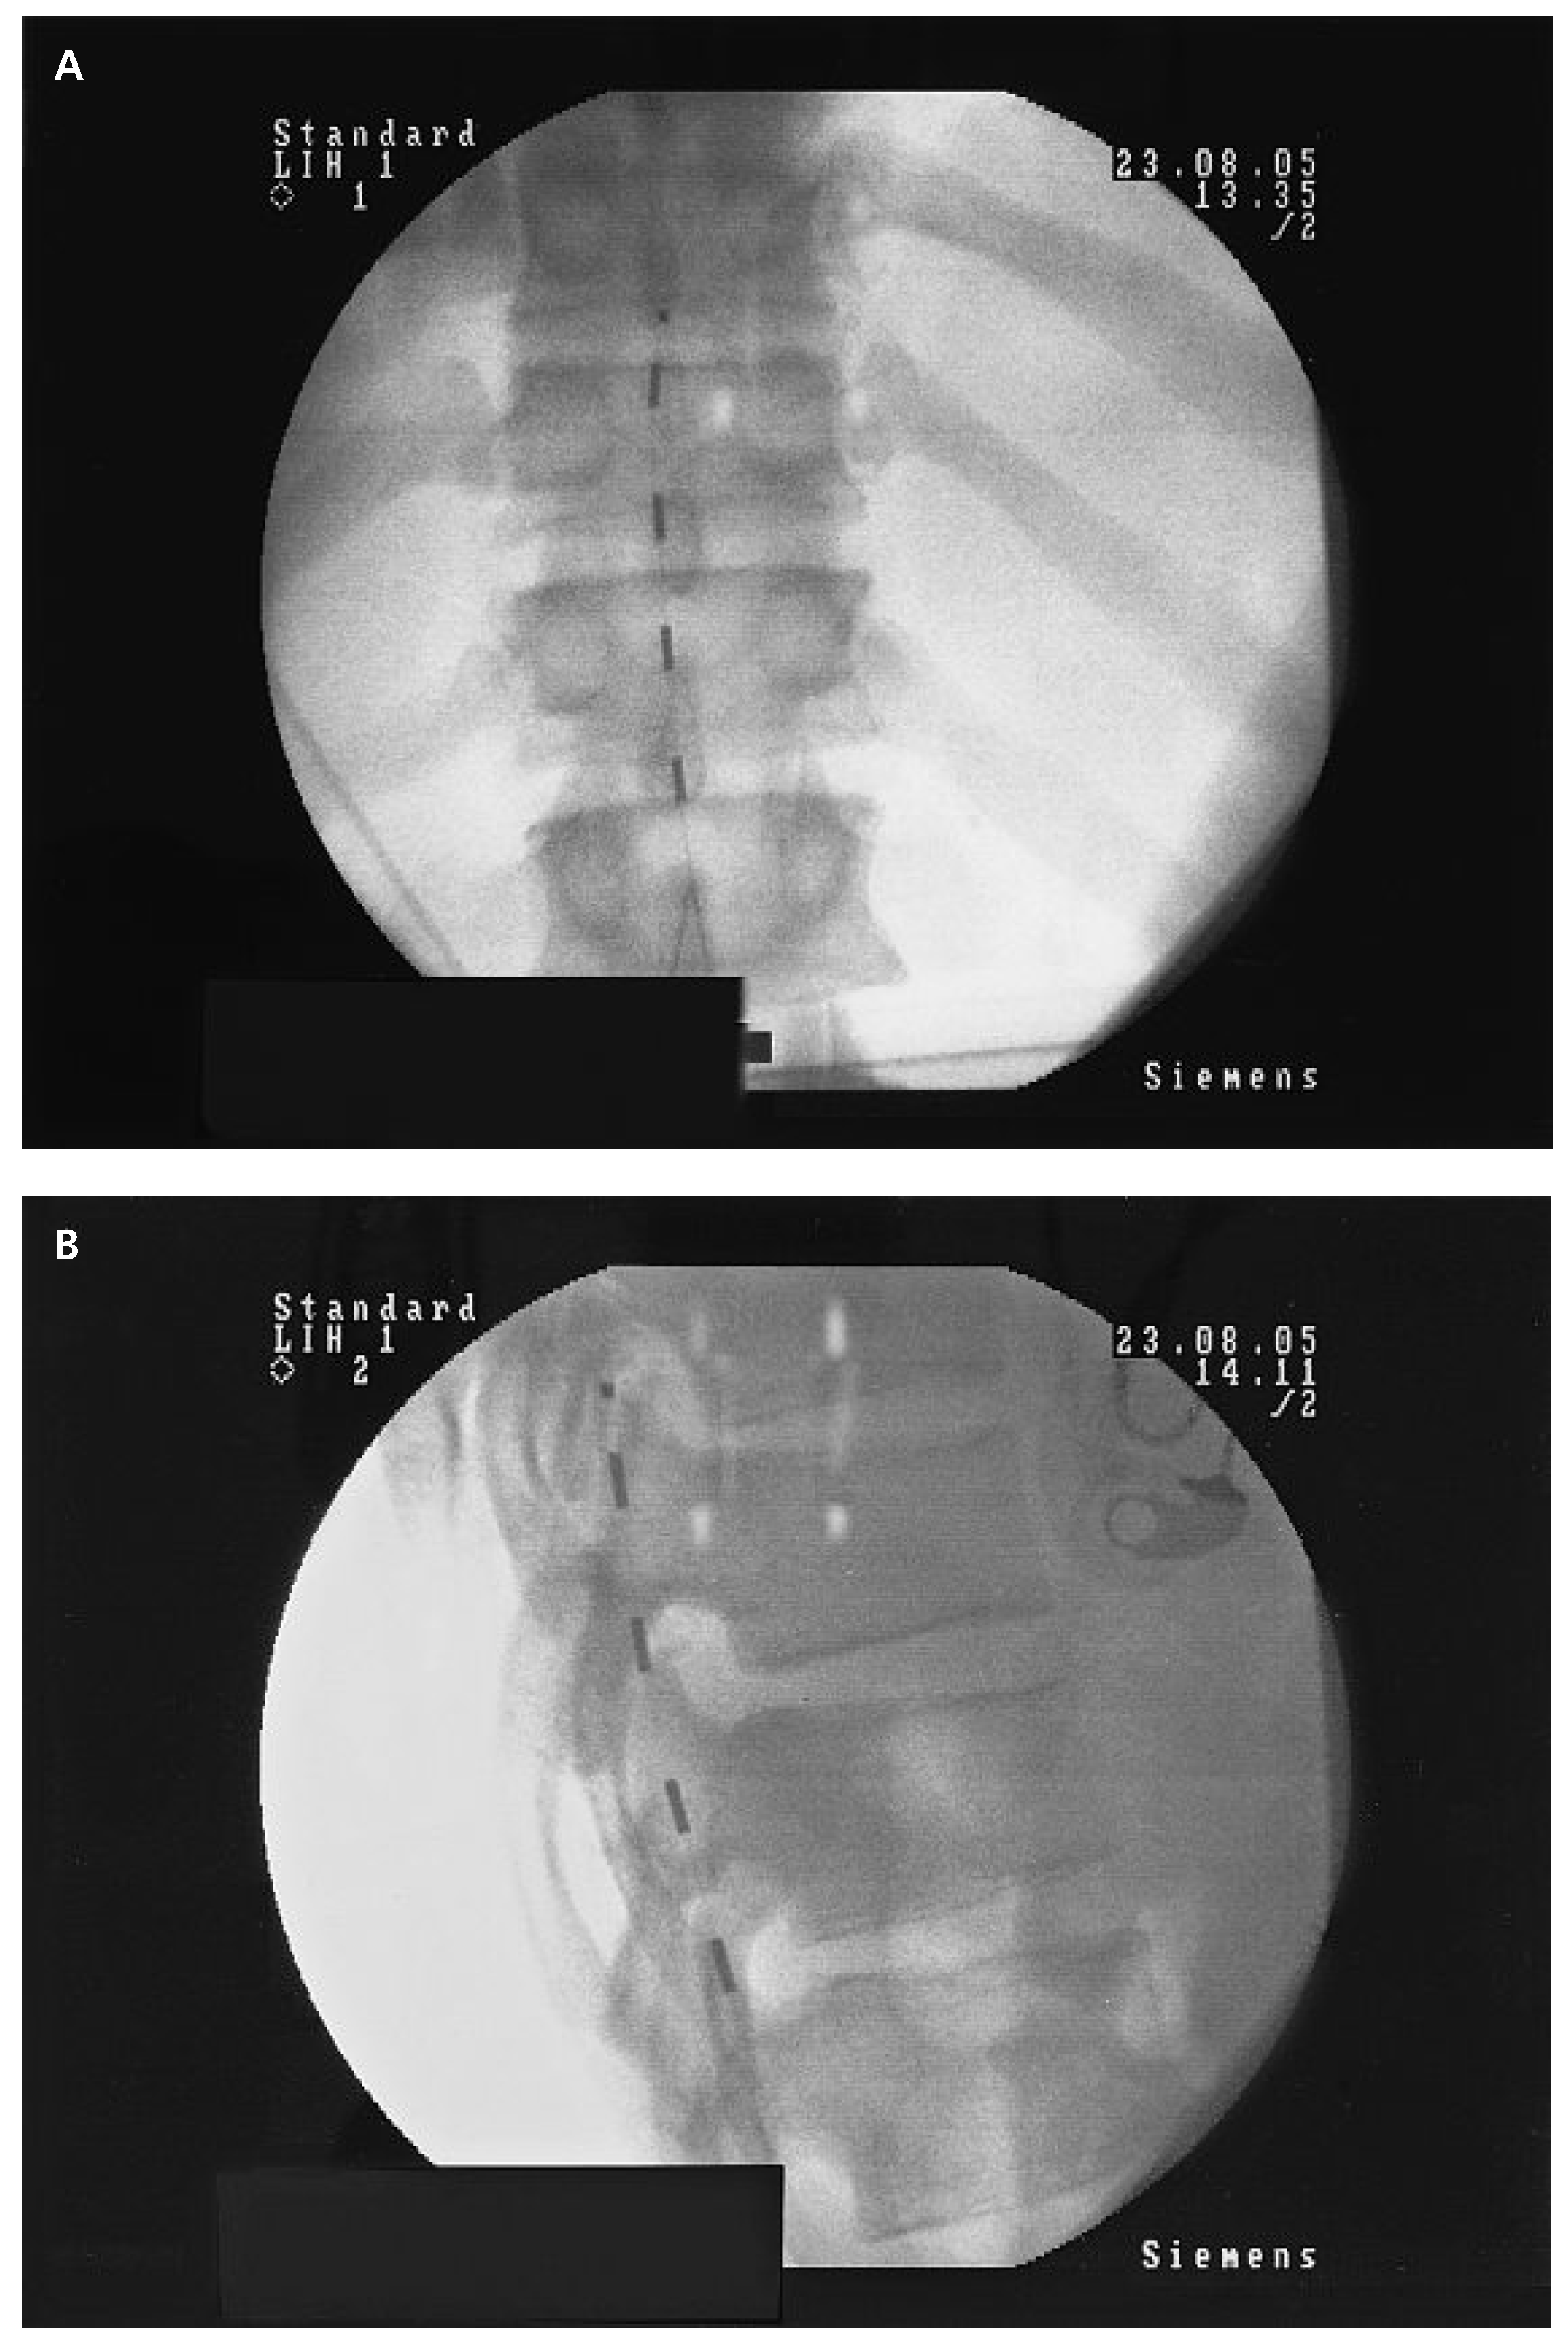

![]() |